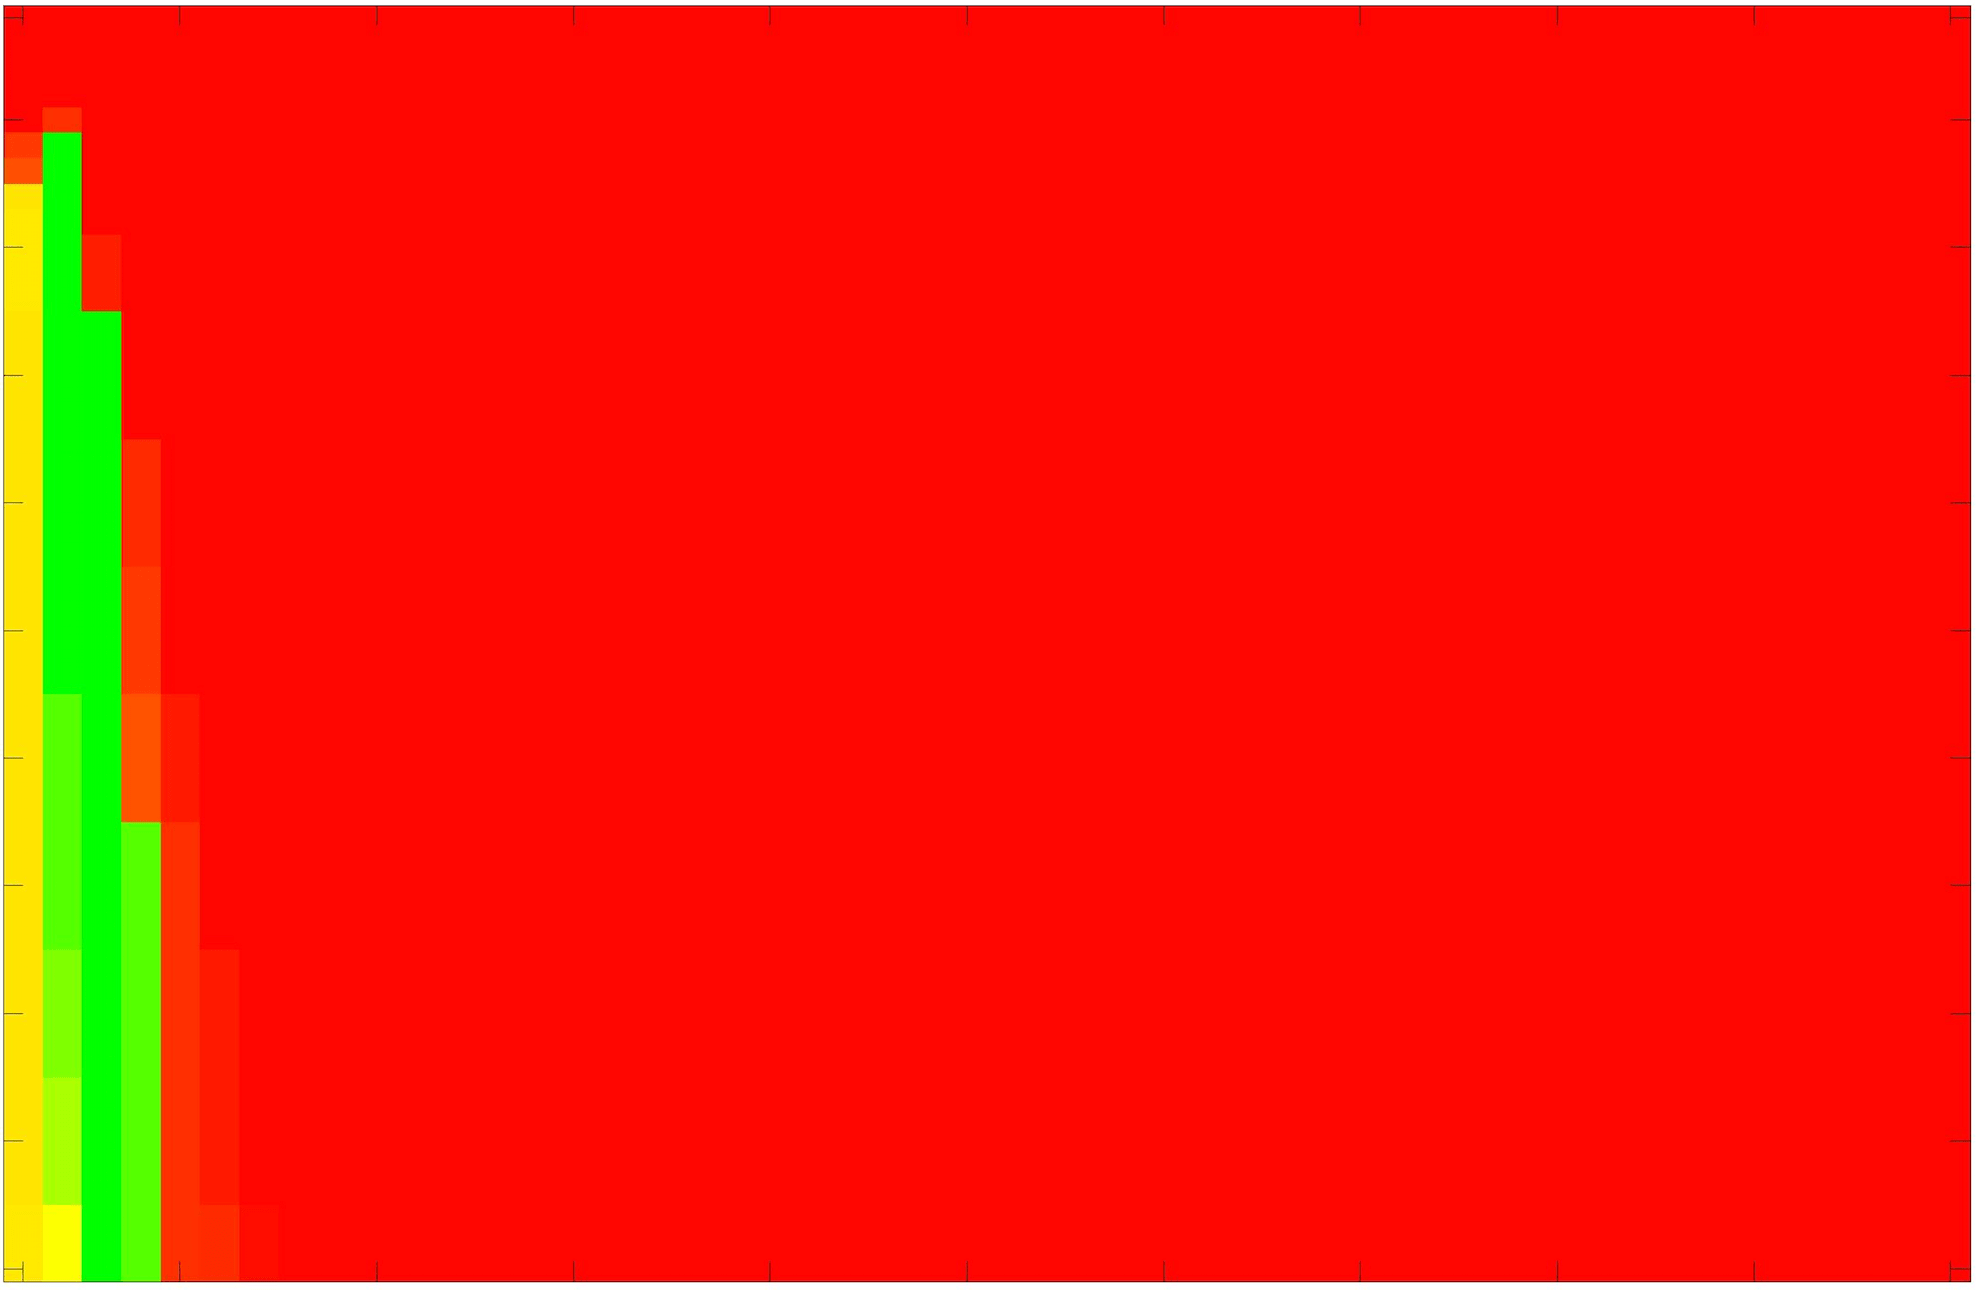

where refers to the number of points in the enclosed region. This takes values in the range , with higher TC values indicating a more accurate segmentation. In the following we will represent accuracy visually from red () to green (), with the intermediate scaling of colours used shown in Fig. 8. This will be particularly relevant in §7.2.

The TC values for the parameter sets are presented as heatmaps in Figs. 11–13. A heatmap is a convenient way to display accuracy results for hundreds of tests concisely. In Fig. 9 we give an example heatmap with the same axes used for those in Figs. 11–13. For each of the combinations of parameter values we give the TC value of the segmentation result and represent it by the appropriate colour. The corresponding colour scale is shown in Fig. 8. Qualitatively, the more green areas of the heatmap the more accurate the model is for a wider set of parameters. Example results for Test Image 5 when varying (with ) for the proposed model are given in Fig. 10. Here it can be seen what each accuracy result corresponds to visually.

Note. The axes have been removed from the heatmaps in Figs. 11–13 for presentational clarity. However, to be explicit, the axes used in all heatmaps are the same as those in Fig. 9.